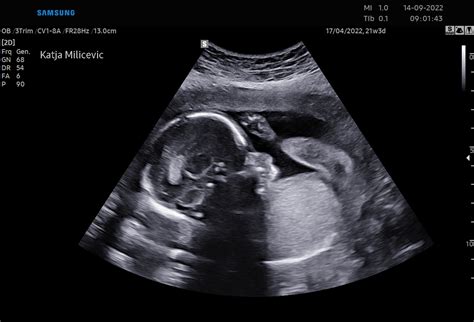

Bi rekla, da pod tvojim srcem raste fantek ali punčka? Pri 19. tednih te to gotovo zelo zanima in komaj čakaj ultrazvok, ki ti bo dal odgovor na to vprašanje. Večino staršev najbolj neučakano pričakuje ravno to informacijo, vendar pa to ni edina razburljiva informacija, ki jo tam dobita. Zdravnik bo plod podrobno pregledal, da se prepriča, da vsi vitalni organi izgledajo in delujejo tako, kot morajo. V tem tednu ali v naslednjem tednu vas morda čaka morfologija ploda, zelo pomemben pregled, kjer zdravnik celovito pregleda otrokovo telo, vključno z delovanjem možganov, srca in hrbtenice.